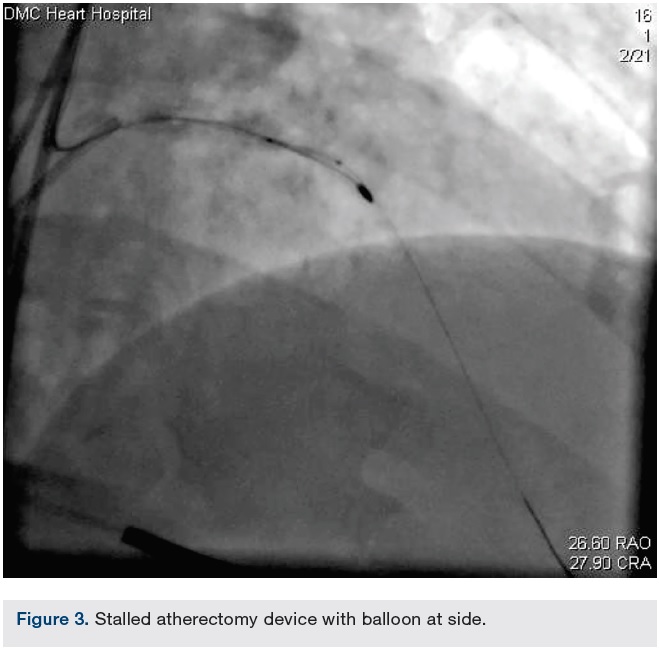

Femoral access was obtained. The LM was engaged with a second guide (Xtra Backup [XB] 3.5 guide). A BMW wire was negotiated to the distal LAD beyond the burr. Multiple inflations of a 1.5 x 12 mm balloon were performed beside, proximal, and distal to the burr. This was followed by serial inflations using a 2.0 x 12 mm balloon. A slight tug on the Rota burr was then successful in retrieving it.